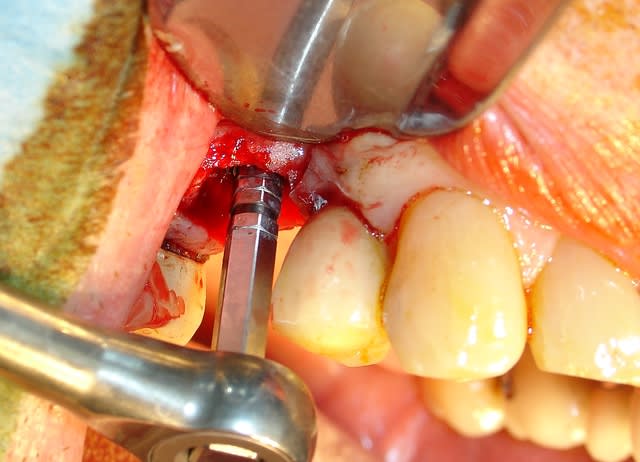

Il existe 2 solutions pour le retirer la piezzo ou le trépan.

J'ai donc choisi cette dernière solution très rapide.

Je vous laisse regardé les images.

Le remplacement c'est fait par un AnyRidge de chez MegaGen de diamètre 5 et longueur 10. J'ai juste profiter de la situation pour re-combler là ou en 2007 on avait mis de l'os autogène....mais ou est il passé? Le comblement a été fait avec une recette maison à base de PRF os bovin et bétaTCP.